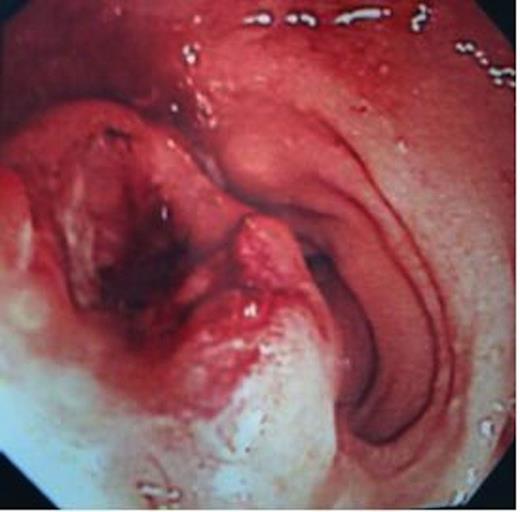

She underwent colonoscopy, which revealed a fungating tumour at 10 cm from the anal verge in the rectum and rest of the colon was normal (Figure 1). The histopathological examination of the biopsy revealed a poorly differentiated invasive adenocarcinoma (Figure 2).

Haematoxylin and Eosin staining of the biopsy specimen. Tumour overlying the large bowel mucosa with the line demarcating the tumour edge with arrow pointing at the body of the tumour (magnification×4).